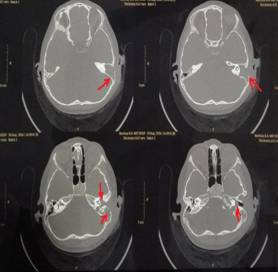

該患兒既往無中耳炎及耳流膿病史,僅表現(xiàn)為1個月前耳后稍有紅腫、疼痛,在當(dāng)?shù)蒯t(yī)院曾被診斷為“蚊蟲咬傷”所致,家長也未引起足夠的重視。近半月來,患兒耳后紅腫疼痛加重,遂到我市某三甲醫(yī)院就診,行高分辨率中耳乳突CT,發(fā)現(xiàn)側(cè)顱底、中耳乳突腔巨大新生物占位,乳突骨皮質(zhì)破壞吸收,并可疑耳后骨膜下膿腫形成。病情若進(jìn)一步發(fā)展,膽脂瘤破壞顱底骨質(zhì),將極有可能并發(fā)腦膜炎、腦膿腫,甚至出現(xiàn)敗血癥、腦疝等,危及生命。

1.術(shù)前耳后紅腫 2.術(shù)前CT1

3.術(shù)前CT2 4.術(shù)中術(shù)腔中的巨大膽脂瘤